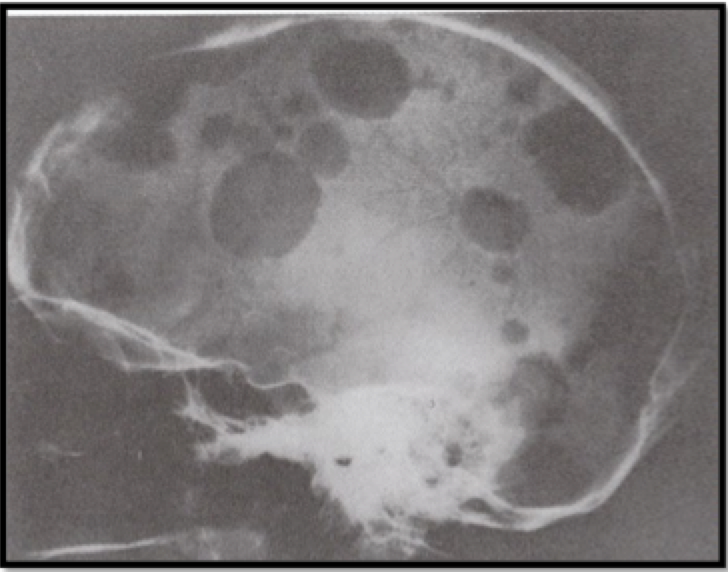

Lesi yang ditunjukkan pada foto rontgen di bawah ini adalah

A. Myeloma multiple

B. Kista epidermoid

C. Fibrous displasia

D. Granuloma eosinofilik

E. Hemangioma

A